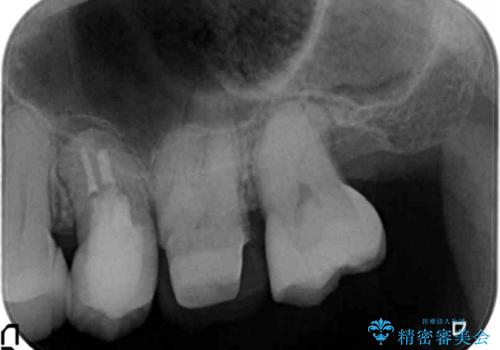

特に割れている所見はなかったため、根の治療から被せ物まで治療を行いました。

奥の銀歯のやりかえも希望されたため、セラミッククラウン、インレーにする治療をしています。

- 合計 48.4万円( 左上5:再根管治療 9万円、ファイバーコア2万円、仮歯1万円、ジルコニアクラウン10万円 左上6:仮歯、ジルコニアクラウン 左上7:emaxインレー7万円)費用は治療当時の料金となります

左上6番のアンレーは、歯の破折を防ぐためにクラウンとしました。